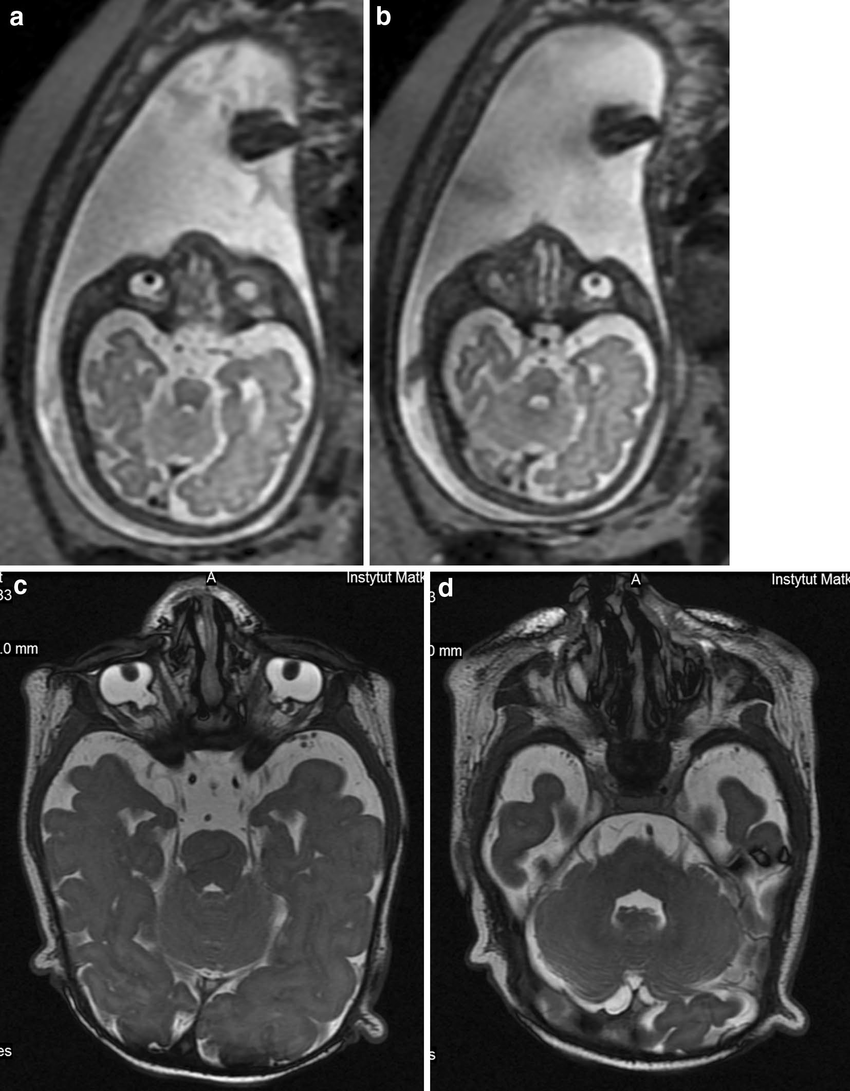

Fetal MRI (Magnetic Resonance Imaging) is an advanced diagnostic tool used to obtain detailed images of a baby’s internal organs while in the womb. It is especially valuable when ultrasound findings are unclear or when a more precise evaluation of fetal abnormalities is required. Fetal MRI is safe, non-invasive, and provides exceptional clarity without using radiation.